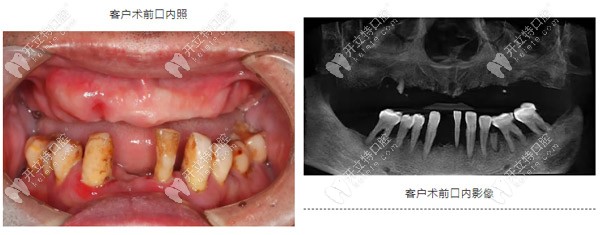

67歲,男,重度牙周炎二十多年,缺失牙十多年,一直戴活動(dòng)義齒,但因?yàn)榱x齒的固位不太好,使用不方便。

重度牙周炎導(dǎo)致上頜牙齒缺失

1、牙齒有重度牙周炎,造成了牙槽骨的重度流失;

2、前牙區(qū)牙槽骨寬度不夠,骨量狹窄;

3、后牙區(qū)骨高度不足,需要進(jìn)行斜型種植;

4、上頜竇腔偏斜,特別考驗(yàn)種植體的位置精準(zhǔn)度,方向需要與竇腔平行;

5、上唇豐滿度不夠,需要進(jìn)行前牙植骨